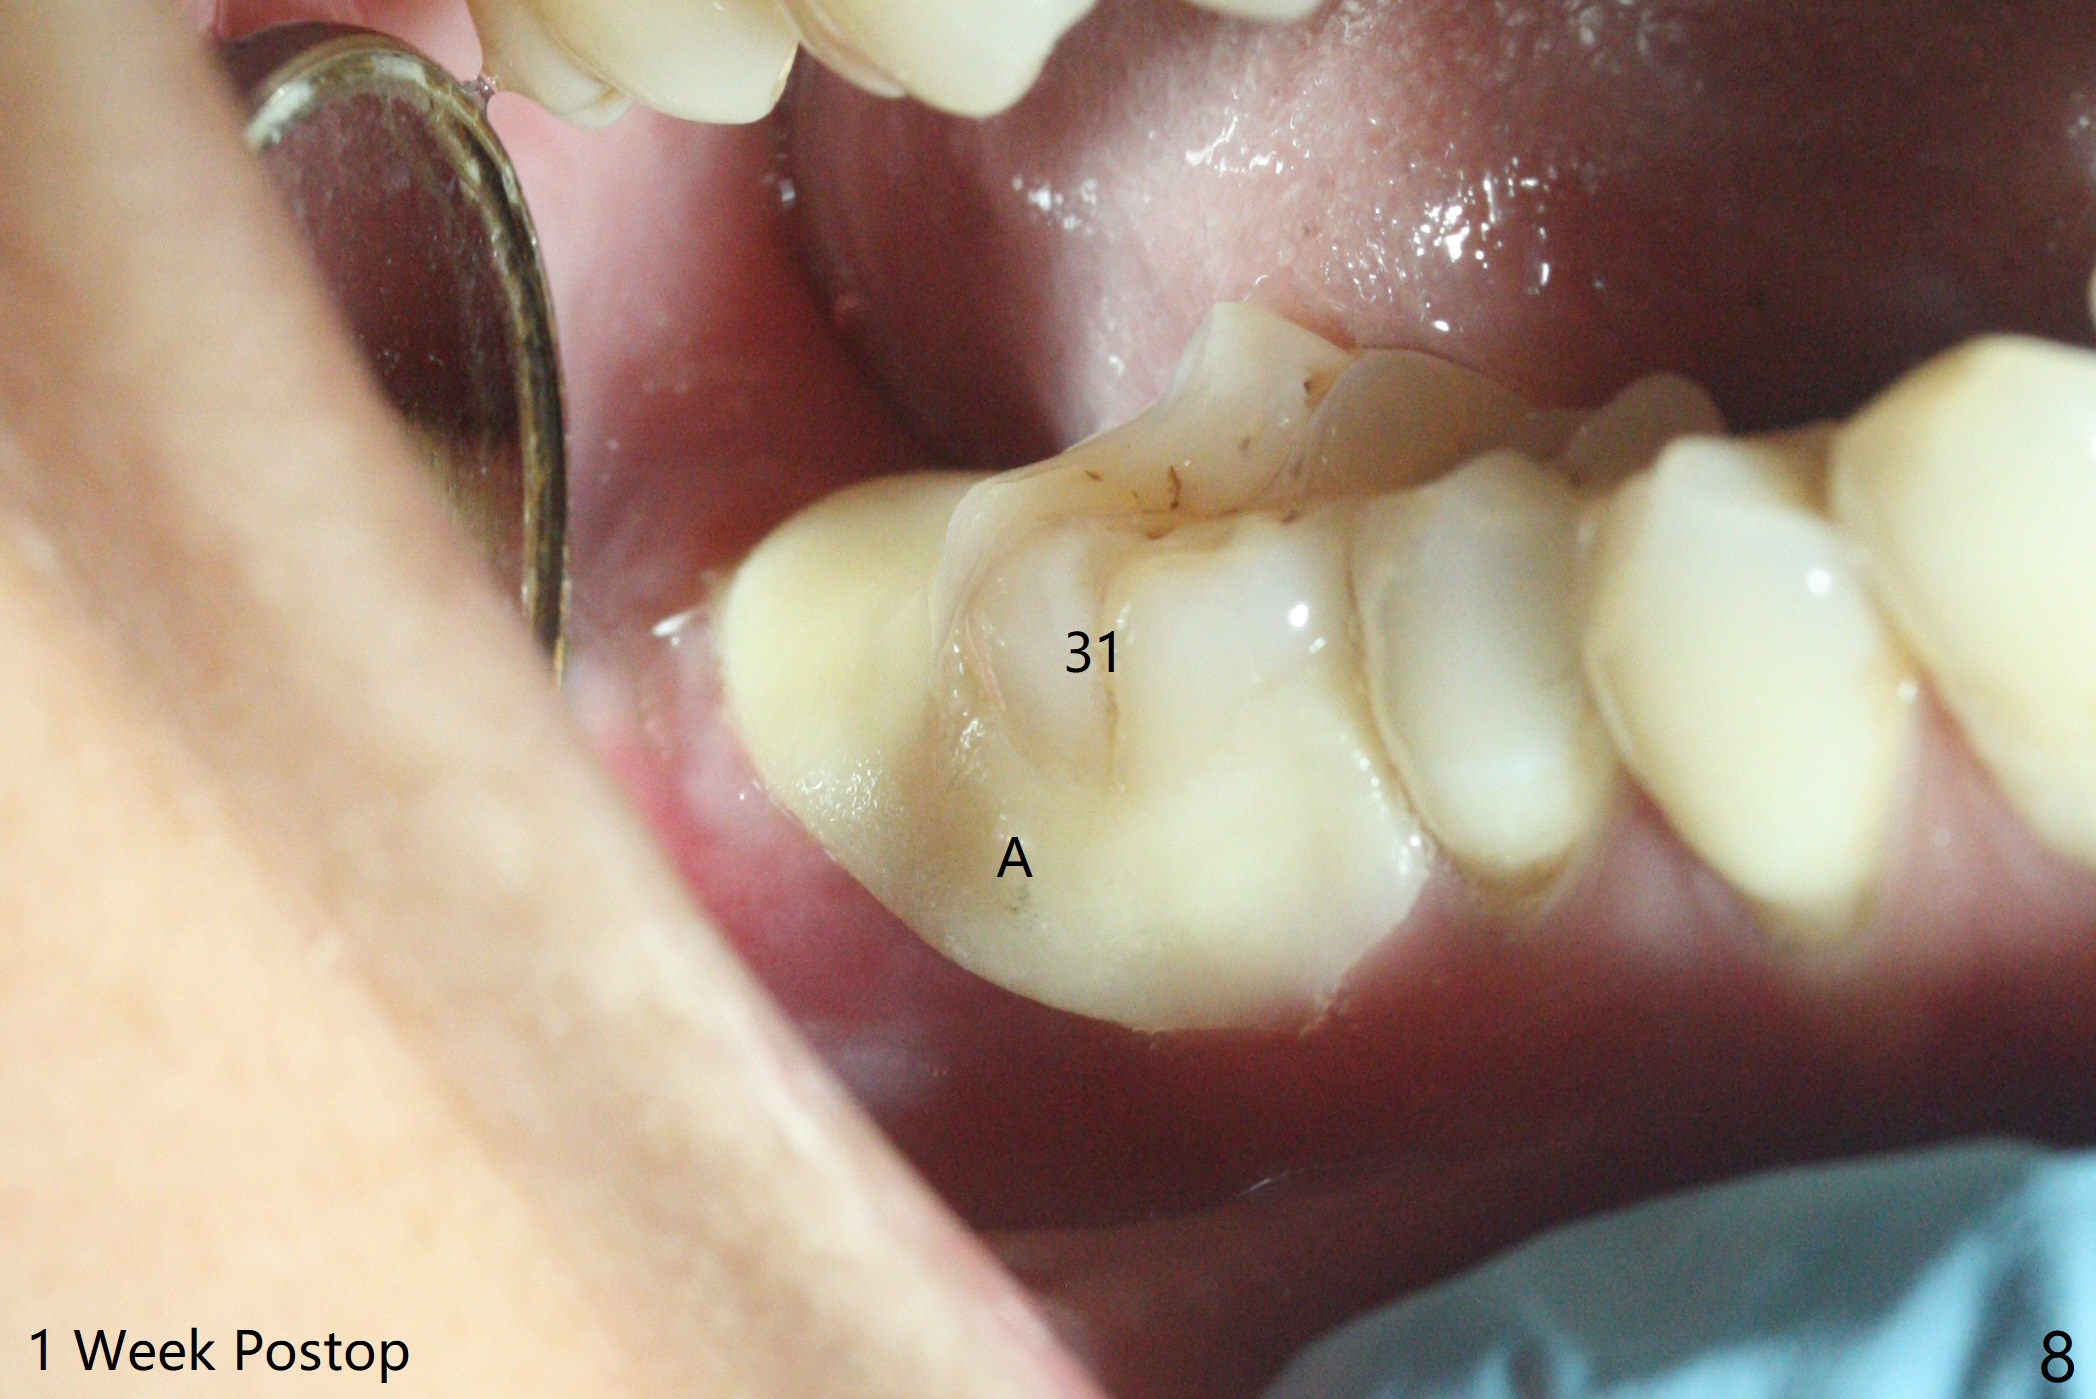

31号牙拔除前近中颊侧有一个瘘道(图一:<),说明32号牙被感染可能性小。术中发现虽然一小部分智齿牙冠与第二磨牙巨大牙槽窝相通(图二:*),但是病变并没有往智齿周围发展(S(可能是牙囊));借助导板(9毫米offset)毫无困难完成钻洞,但是嫌钻洞深度不够。由于植体扭力低(<10 Ncm),只好放置粘性骨粉(图三),覆盖PRF和Cytoplast,PTFE缝线,以及树脂敷料。病人左下第二磨牙缺失多年,牙槽嵴粘膜出现白色病变(图四:箭头),可能与对合磨牙延申有关(图五:箭头)。如果这个牙位需要导板植牙,垂直距离将是一个严峻问题。即种导板(图六:31)与延期导板(18)金属圈放置有不同,相差1.5毫米(图七):即种(由于拔牙)金属圈可以放低,而愈合牙位(由于牙龈存在)金属圈必须放高。所以第二磨牙即种有足够垂直空间优势。术后一周复诊,老的树脂敷料不牢(因为下面没有基台),脱落,下面不可吸收膜没有外翻,重新制作敷料(图八:A)。术后一个月由于2,3号牙之间牙周炎发作,树脂敷料牢靠,下面不可吸收膜稍微暴露,两者取出后,植体略微暴露。没有基台,骨粉固定好像不佳。